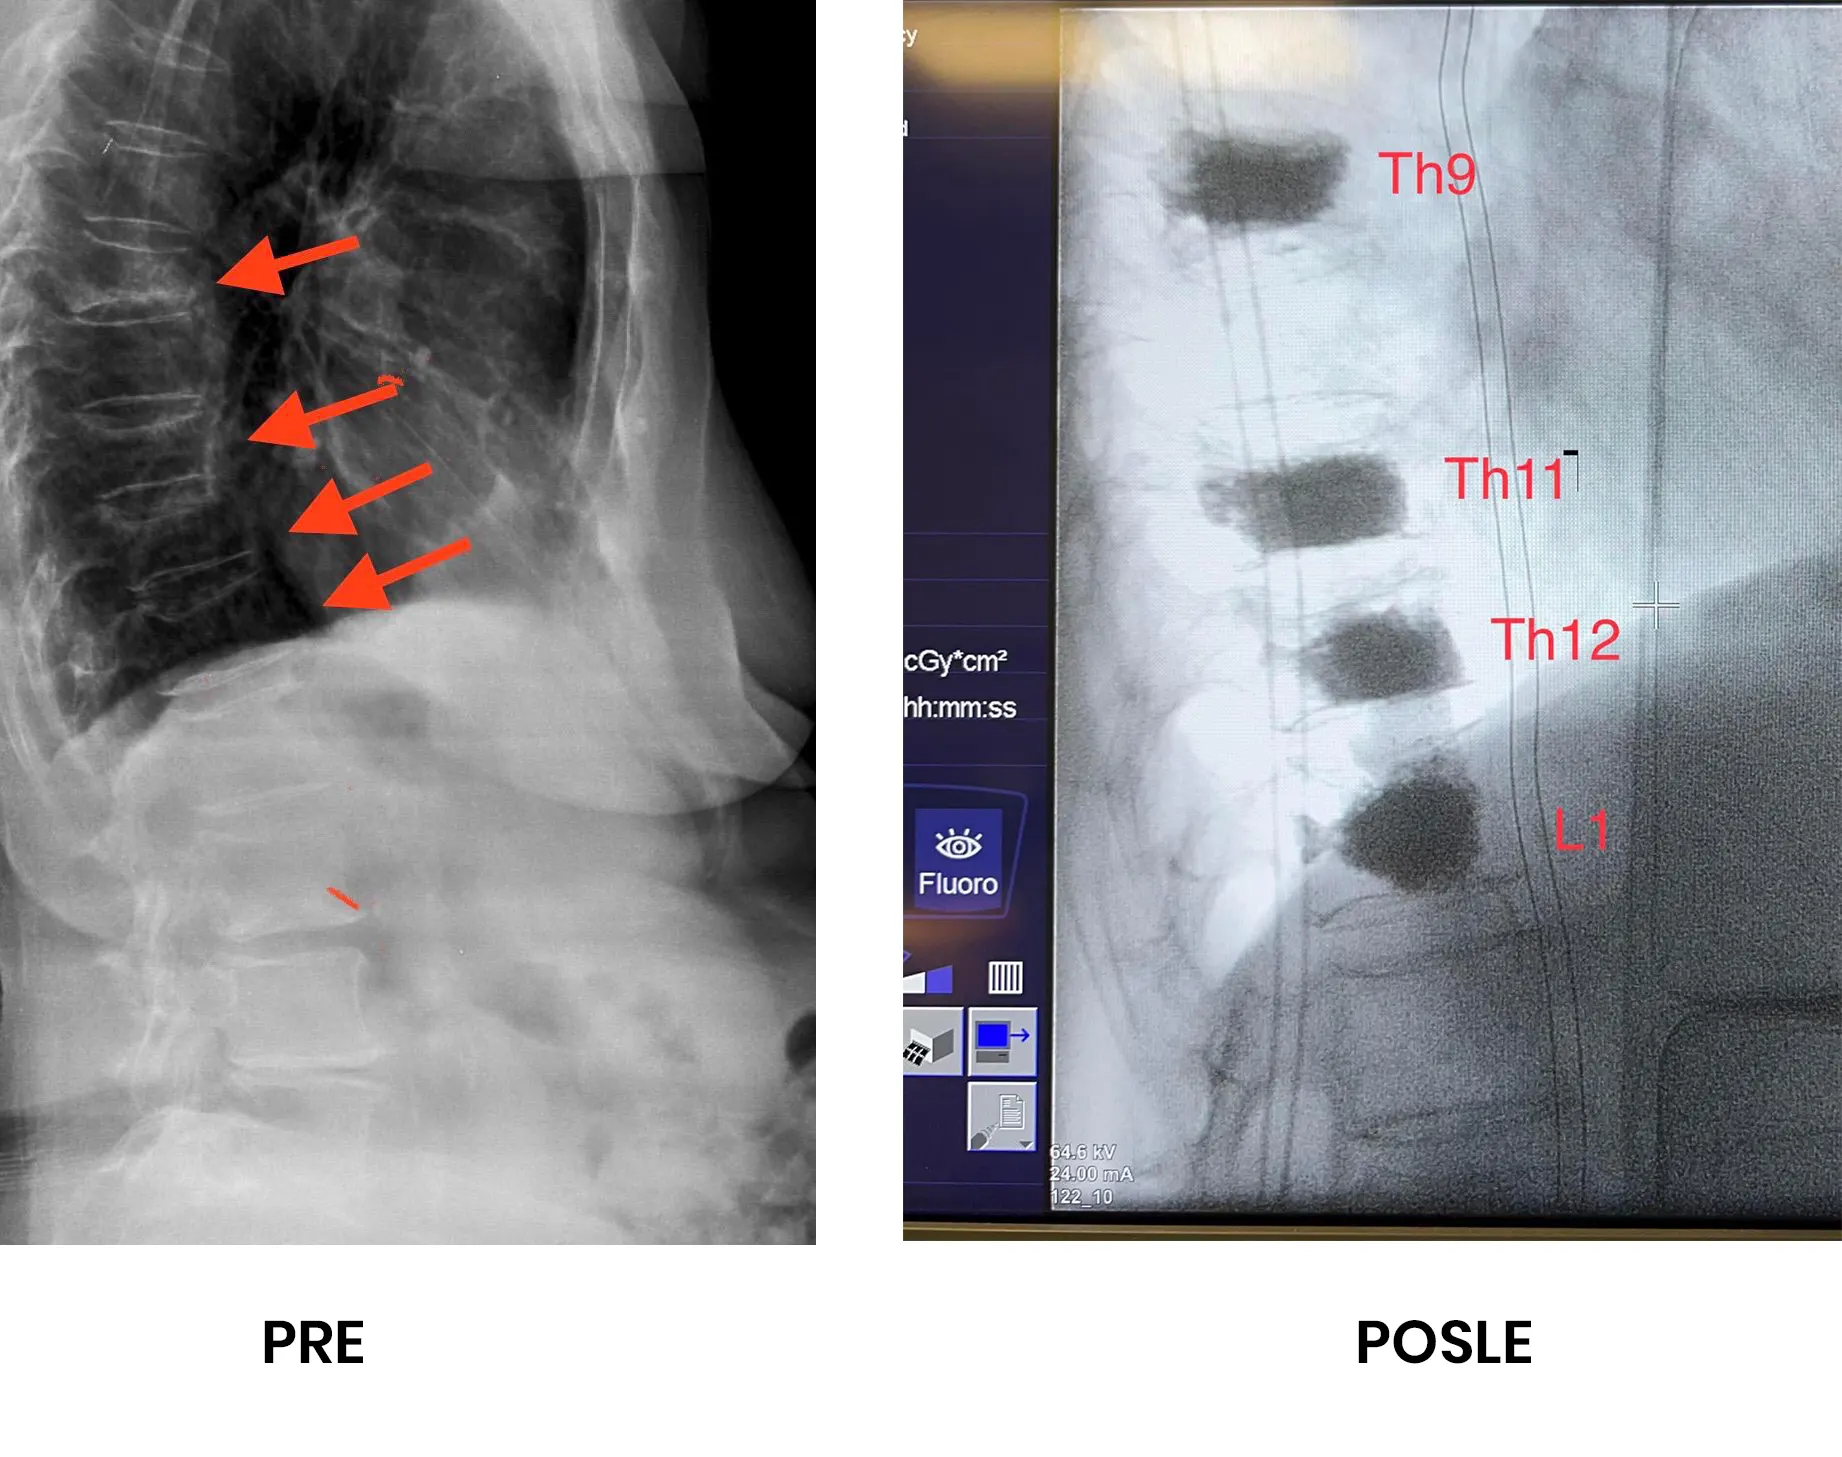

Pacijentkinja od 83 godine, sa naglo nastalim nepodnošljivim bolom u leđima. Ima dokazanu osteoporozu. MR i RTG kičme pokazao je postojanje kompresivnih preloma četiri pršljena, zbog generalizovanja osteoporoze.

Intervencija urađena u lokalnoj anesteziji, bez klasičnog reza kože. Preko kože plasirane su igle u slomljena tela pršljenova i ubrizgan specijalni cement kojim su pršljenovi učvršćeni i istovremeno potpuno otklonjen bol.

Perkutana vertebroplastika kod preloma kičme zbog osteoporoze.